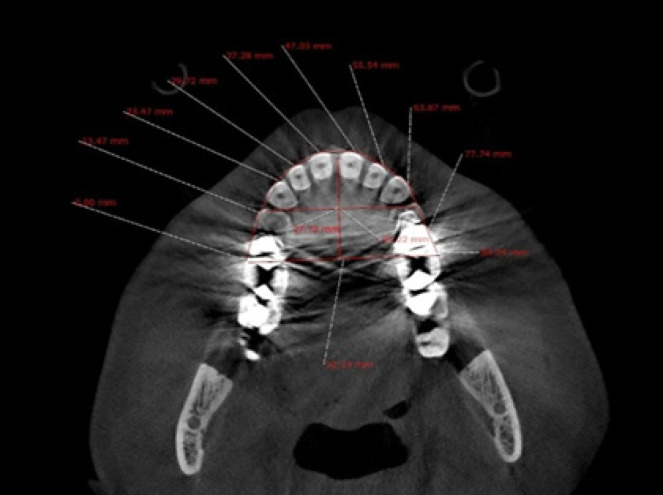

Methods: CBCT records taken during 2020-2022 of 120 patients were obtained to investigate the relationship between impacted canine and maxillary morphology as well as sinus dimensions. The CBCT images were then divided into three groups: control, unilaterally canine impaction and bilaterally canine impaction. Then morphology-related variables (arch circumference, arch length, inter molar width, inter first premolar width, palatal depth, anterior posterior dimension of the right and left sinuses, and mediolateral dimension of the right and left sinuses) were analyzed and compared between groups. All measurements were done by Ondeman 3D dental software. Statistical analysis was carried out by SPSS software version 21 using one-way ANOVA.

Results: There were meaningful differences in patients with canine impaction compared with control group in arch circumference (P value= 0.004) and arch length (P value= 0.001), inter molar width (P value= 0.001), inter first premolar width (P value= 0.001), mediolateral dimension of the right (P value=0.001) and left (P value= 0.001) sinuses of maxilla. Furthermore, Palatal depth and anterior posterior dimension of the right and left sinuses did not show statistically significant difference between groups.